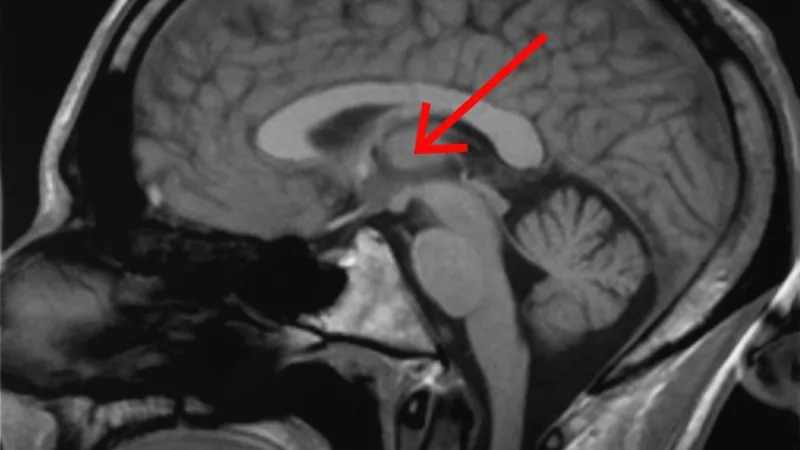

Většina expertů na konferenci se shodla na tom, že pro to, čemu se říká vědomí, jsou zásadní některé konkrétní vlastnosti a oblasti mozku. Patří mezi ně hlavně soubor spojení mezi thalamem (česky hrbol mezimozkový), který přijímá a předává smyslové a motorické informace z těla, a mozkovou kůrou, kde se tyto informace dále zpracovávají. Proč je to důležité s ohledem na vývoj člověka před narozením? Nové studie mozku plodu totiž prokazují, že základy tohoto spojení jsou vytvořené kolem 24. týdne vývoje.